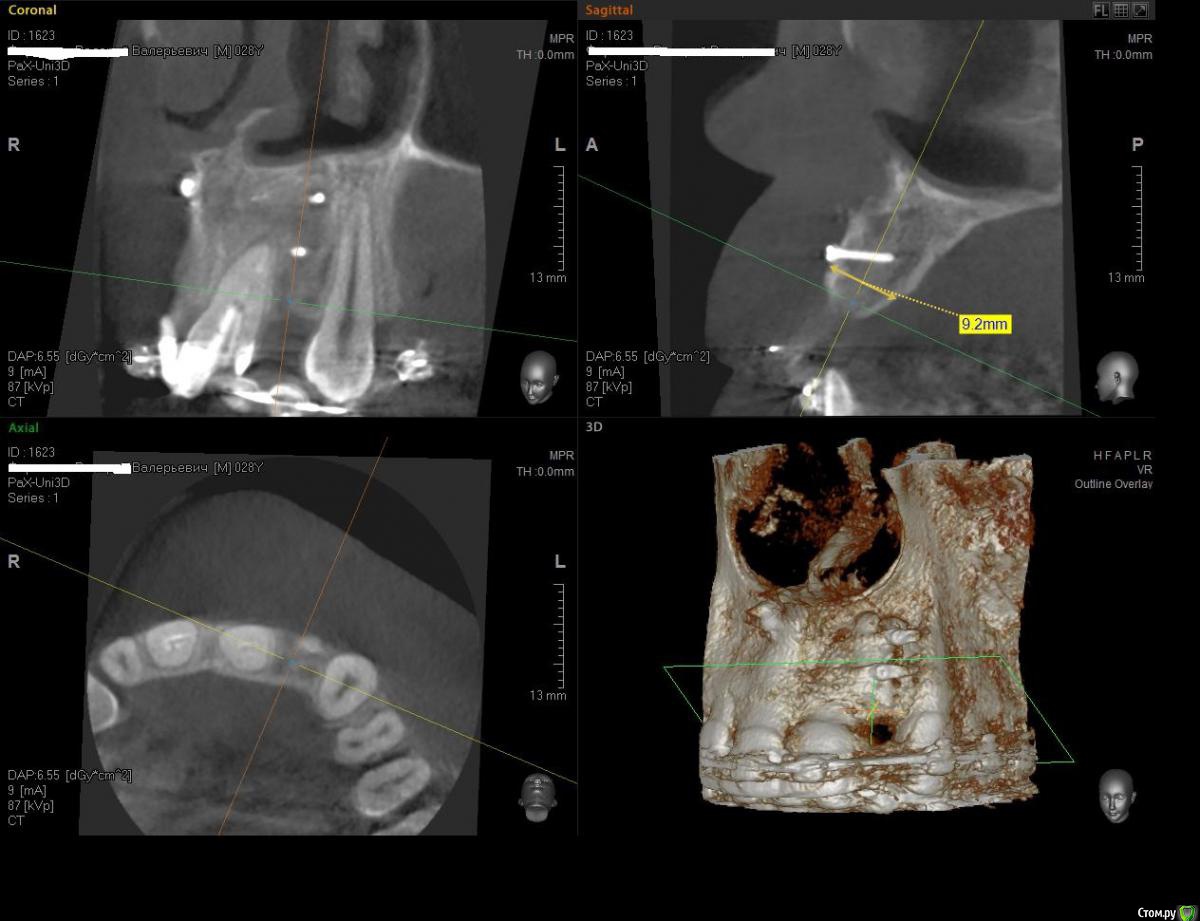

Kostoprav Опубликовано 8 июля, 2015 Поделиться Опубликовано 8 июля, 2015 ИЗНАЧАЛЬНАЯ СИТУАЦИЯ ПОЛУЧИЛОСЬ сори что нет фото до имплантации. Блок взял с тела челюсти, фиксировал двумя винтами (во время имплантации выкрутил только один), присыпал gen os, укрыл дермой-получил заметный прирост слизистой) имплант альфадент 3,75х11,5 2 Ссылка на комментарий

Mane Опубликовано 8 июля, 2015 Поделиться Опубликовано 8 июля, 2015 (изменено) Видно что блок прирос. Здорово Остальное оценить сложноМне нравится положение импланта в плане оси. Но уровень заглубления не ясенТакже не видно прироста десныВ общем мало данных для оценкиНо опять же вам именно она и нужна? Изменено 8 июля, 2015 пользователем Mane Ссылка на комментарий

Kostoprav Опубликовано 8 июля, 2015 Автор Поделиться Опубликовано 8 июля, 2015 Видно что блок прирос. ЗдоровоОстальное оценить сложноМне нравится положение импланта в плане оси.Но уровень заглубления не ясенТакже не видно прироста десныВ общем мало данных для оценкиНо опять же вам именно она и нужна?по вестибюлярной поверхности заглубил приблизительно на 1мм с небной больше получилось. слизистая по сравнению с первым разом значительно толще стала, доказать к сожалению не могу так как не делал фото(: я выложил этот пост не только ради оценки, может кому из начинающих данный случай сгодиться 3 Ссылка на комментарий

Maxfac Опубликовано 8 июля, 2015 Поделиться Опубликовано 8 июля, 2015 по вестибюлярной поверхности заглубил приблизительно на 1мм с небной больше получилось. слизистая по сравнению с первым разом значительно толще стала, доказать к сожалению не могу так как не делал фото(: я выложил этот пост не только ради оценки, может кому из начинающих данный случай сгодитьсяНа что ориентировались, позиционируя платформу по вертикали? Ссылка на комментарий

Kostoprav Опубликовано 8 июля, 2015 Автор Поделиться Опубликовано 8 июля, 2015 На что ориентировались, позиционируя платформу по вертикали?ориентацию задавал ортопед, стоял рядом за спиной и командовал Ссылка на комментарий